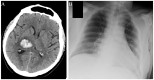

The novel severe acute respiratory syndrome coronavirus 2 (SARS-CoV-2) emerged in Wuhan, China and rapidly spread worldwide, with a vast majority of confirmed cases presenting with respiratory symptoms. Potential neurological manifestations and their pathophysiological mechanisms have not been thoroughly established. In this narrative review, we sought to present the neurological manifestations associated with coronavirus disease 2019 (COVID-19). Case reports, case series, editorials, reviews, case-control and cohort studies were evaluated, and relevant information was abstracted. Various reports of neurological manifestations of previous coronavirus epidemics provide a roadmap regarding potential neurological complications of COVID-19, due to many shared characteristics between these viruses and SARS-CoV-2. Studies from the current pandemic are accumulating and report COVID-19 patients presenting with dizziness, headache, myalgias, hypogeusia and hyposmia, but also with more serious manifestations including polyneuropathy, myositis, cerebrovascular diseases, encephalitis and encephalopathy. However, discrimination between causal relationship and incidental comorbidity is often difficult. Severe COVID-19 shares common risk factors with cerebrovascular diseases, and it is currently unclear whether the infection per se represents an independent stroke risk factor. Regardless of any direct or indirect neurological manifestations, the COVID-19 pandemic has a huge impact on the management of neurological patients, whether infected or not. In particular, the majority of stroke services worldwide have been negatively influenced in terms of care delivery and fear to access healthcare services. The effect on healthcare quality in the field of other neurological diseases is additionally evaluated.

Figures